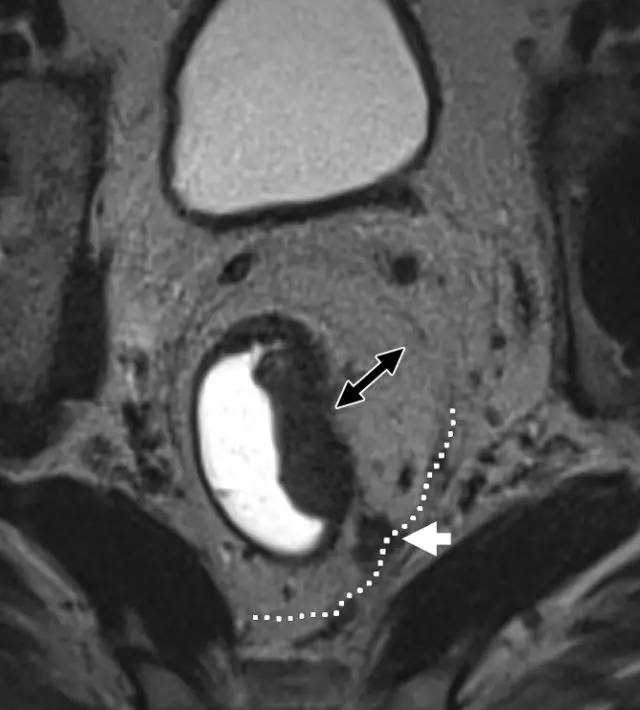

图 31 轴向 T2 加权图像报告 CRM 的距离。T3d 肿瘤局限于固有肌层内,肿瘤毗邻直肠系膜筋膜(箭头;肿瘤为 T2)。侵犯边界似乎是左后方(白色箭头),肿瘤的 CRM 评估为 5 mm。但有两个混合信号强度淋巴结(黑色箭头)邻接直肠,导致 CRM 为 0 mm。

图 32 轴向 T2 加权图像报告 CRM 的距离。T3c 肿瘤,靠近腹膜的 EMVI(白色箭头)和不规则信号强度淋巴结的 T3c 肿瘤,通过毗邻直肠系膜筋膜的淋巴结包膜(黑色箭头)肿瘤扩展(预测 CRM = 0 mm)。

直肠系膜筋膜是包围直肠周围脂肪和直肠的低信号,代表 TME 切除术中的手术切除平面。在 MR 图像上,是进行 TME 手术患者的潜在 CRM。CRM 阳性是局部复发和预后差的一个重要的独立预后因素。

环周切缘 CRM